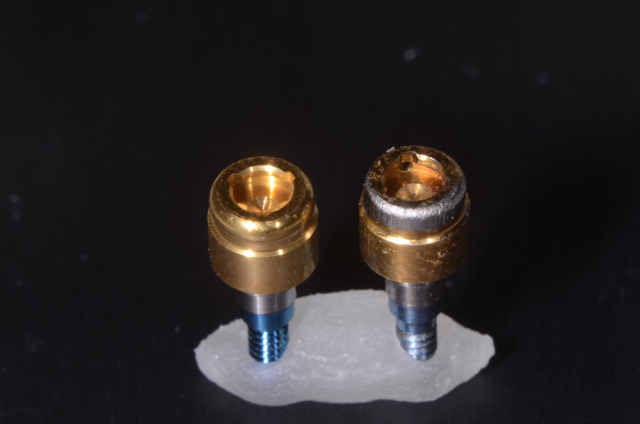

Mary Anne Salcetti | 8 years ago ›A Primer on Locator Abutments for Implant Overdentures

Here's a quick look at the benefits and complications surrounding the use of a locator abutment.